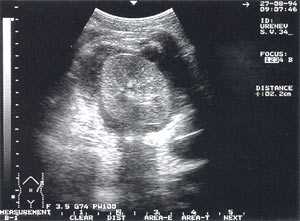

Псевдокисты поджелудочной железы с атипичной локализацией (в печени, селезенке, перидуоденально и т.д.) выявлены у 2 больных - 0,7% (рис. 10).

Рис. 10. Атипично расположенная псевдокиста поджелудочной железы (парадуоденально) в виде анэхогенного образования округлой формы с четкими контурами, однородной структурой, размером до 4,5 см, расположенного рядом с двенадцатиперстной кишкой.